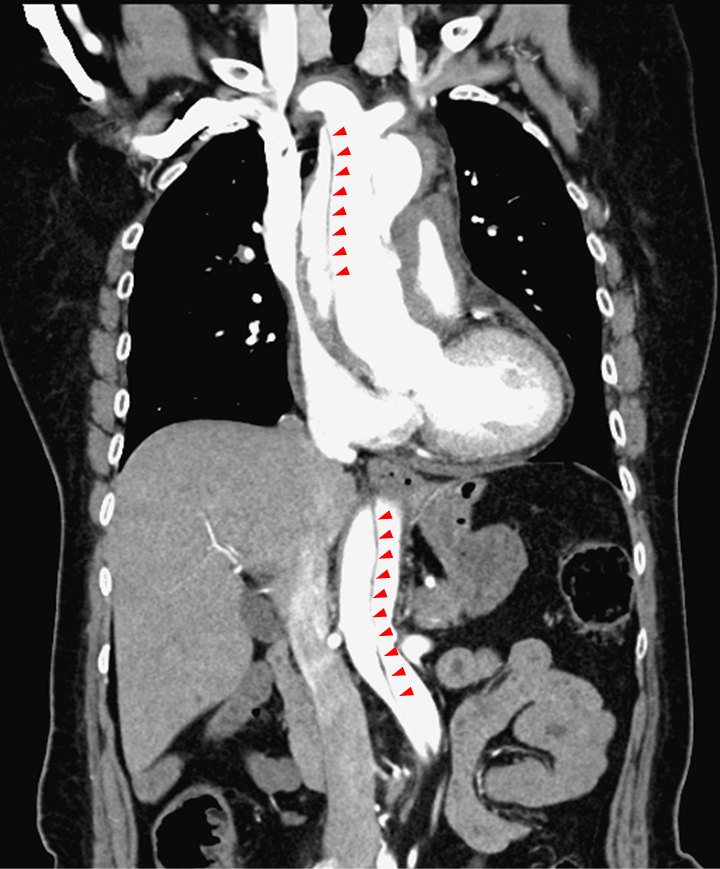

除了劇痛外,主動脈剝離也可能因血流受阻,影響其他器官。圖/北市聯醫

台北市立聯合醫院陽明院區心臟血管內科主治醫師李穎灝指出,主動脈是身體最大的動脈,心臟打出血液後,透過主動脈將血液輸送全身各處。主動脈有三層結構,當血管壁經長年血流沖刷及慢性病摧殘後,內層可能形成裂縫,血液流入內層與中層之間,形成「假腔」,擠壓到「真腔」(正常的血流途徑),導致血液供應受阻。

主動脈剝離依發病位置,分為A、B型。狀如拐杖的主動脈,上行部分稱為升主動脈,轉彎部分是主動脈弓,下行部分則為降主動脈。剝離位置影響到升主動脈的屬於A型,未影響升主動脈的則為B型。A型容易產心臟相關的併發症,死亡率較B型高,若未緊急手術,發病48小時內致死率可高達50%。

除了劇痛外,主動脈剝離也可能因血流受阻影響其他器官。在心臟,可能出現心包膜填塞、心肌梗塞;在腦部,可能導致意識不清、中風等;在腸道,可能導致腸缺血,造成腹痛;甚至可能影響到下肢,腳也會痛。因此,主動脈剝離有「偉大的模仿者」之稱,可能以各種症狀來表現。